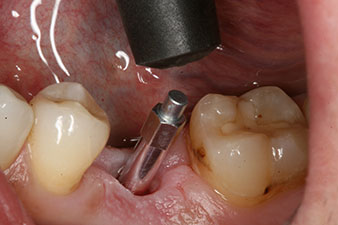

Въртящият момент, използван за машинно-задвижвано поставяне, е 43 Ncm. Освен това, след завинтване на измервателния щифт (SmartPeg), специално пригоден за импланта, стойността на ISQ се измерва със сондата на W&H Osstell ISQ модула.

Този модул е допълнителна екстра към Implantmed на W&H и е закачен към имплантологичния мотор (виж фиг. 11). Липсата на ISQ стойност непосредствено след поставянето е 64 оровестибуларно и 68 мезиодистално (максимална стойност = 100).

Тези стойности могат да показват отворено лечение или дори имедиатно възстановяване. Поради недостатъчния обем на кресталната кост при импланта, областта е подсилена с костните частици, събрани по време на препарацията на имплантното ложе и зашити, за да се изолира слюнката.